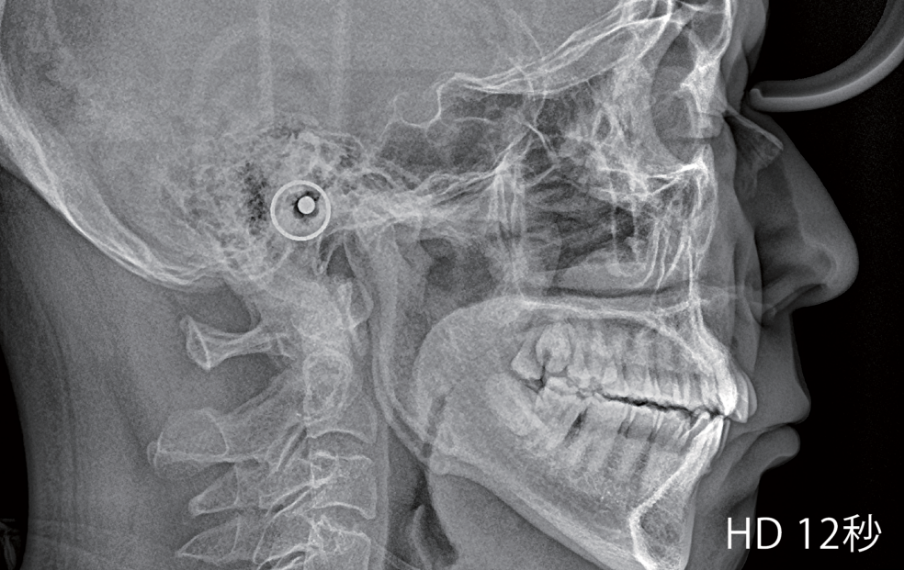

撮影モードは、Fast、Normal、HD(High-Definition)の3段階から画質を選択することができます。

スキャンタイプ、ワンショットタイプの仕様から選択可能。

ワンショットタイプは最短0.2秒、スキャンタイプは最短2秒(Ultra fastモード)で撮影ができます。

高速セファロで患者さんの被ばく線量を最小限に抑えつつ、動きによるブレを最小化することで正確かつ鮮明な画像が得られます。

ワンショットセファロは動きによるブレを最小化し、歪みのない高解像度画像が得られます。

スキャンタイプ仕様では、Ultra fast、Fast、Normal、HDの4段階から画質を選択することができます。